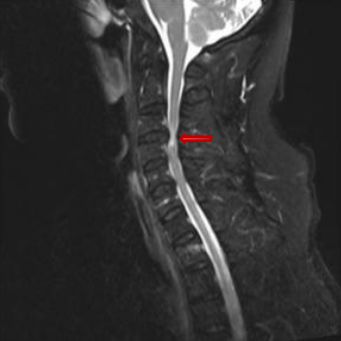

术前MRI。

脊髓受压、变形。